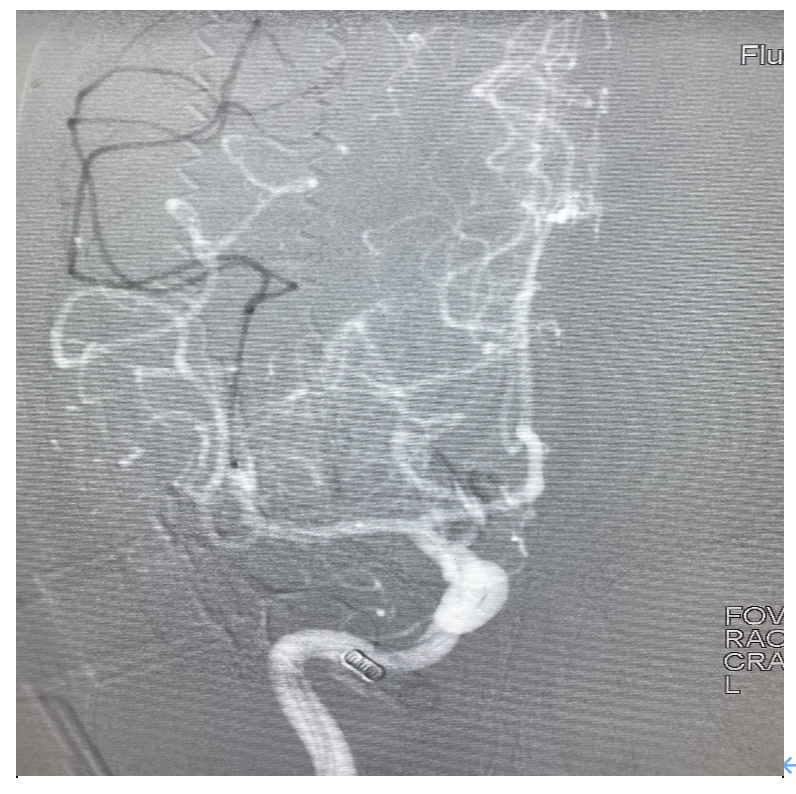

4、给予替罗非班后为进一步了解病变,行3D造影,最终证实M2分叉部一共有4支,开通3支,还有1支闭塞,指向额叶供血。

5、工作位路图,在中间导管高到位辅助下微导管超选M2闭塞分支,冒烟证实血管真腔,释放心玮4-20取栓支架。

6、关闭滴注,中间导管到达M2分叉部,缓慢轻拉支架入中间导管整体撤出体外,可见支架远端附着血栓。 术后即刻造影,闭塞分支血管再通,M2闭塞处的可疑血栓消失,至此4支血管全部通畅,血流3级,结束手术。

此病例是典型的MeVO,闭塞部位为右侧M2段上干的远端,我们选择心玮较小的取栓支架4-20进行取栓是可行的,抽拉结合取栓后3D造影,发现原有闭塞的部位就在上干分叉部,且共有4个分支,取通3支,还有1支向额叶供血的分支未通,术中一度纠结,到底要不要继续取分支血管?分析认为,分支闭塞应该是继发的血栓逃逸,该病例给了静脉溶栓,血栓负荷量并不是很大,而且患者术前有失语的症状,能开通那是锦上添花,就看能否超选成功,起始部虽然成直角,中间导管到位很高,超选倒是容易,但血管还是很迂曲,直径应该在1mm以下,小心释放心玮4-20支架,部分释放在中间导管内,谨小慎微,只想尝试一把,结果运气很好,血栓成功取栓,4支血管全部通畅,术后迅速改善了患者的症状。